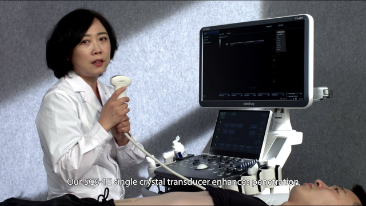

Weniger Stethoskope, mehr Ultraschall?

Optimierte OBG-Workflows sind n?tig, wenn gro?e Patientinnenzahlen im Rahmen von Gesundheitsscreenings bew?ltigt werden sollen. Zum Beispiel sind Fehlbildungen des zentralen Nervensystems (ZNS) eine der h?ufigsten angeborenen Anomalien. Wegen verschiedener f├╝r die Bildgebung ung├╝nstiger Bedingungen, etwa eine schwierige Position des F?tus, ist es besonders schwer, die MSP von 2D-Ultraschall zu erhalten. Aus diesem Grund k?nnen automatisierte Erkennung und Messungen die Scanning-Effizienz deutlich steigern.